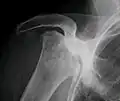

Avascular necrosis most commonly affects the ends of long bones, such as the femur. Other common sites include the humerus (upper arm),[6][7] knees,[8][9] shoulders,[6][7] ankles and the jaw.[10]